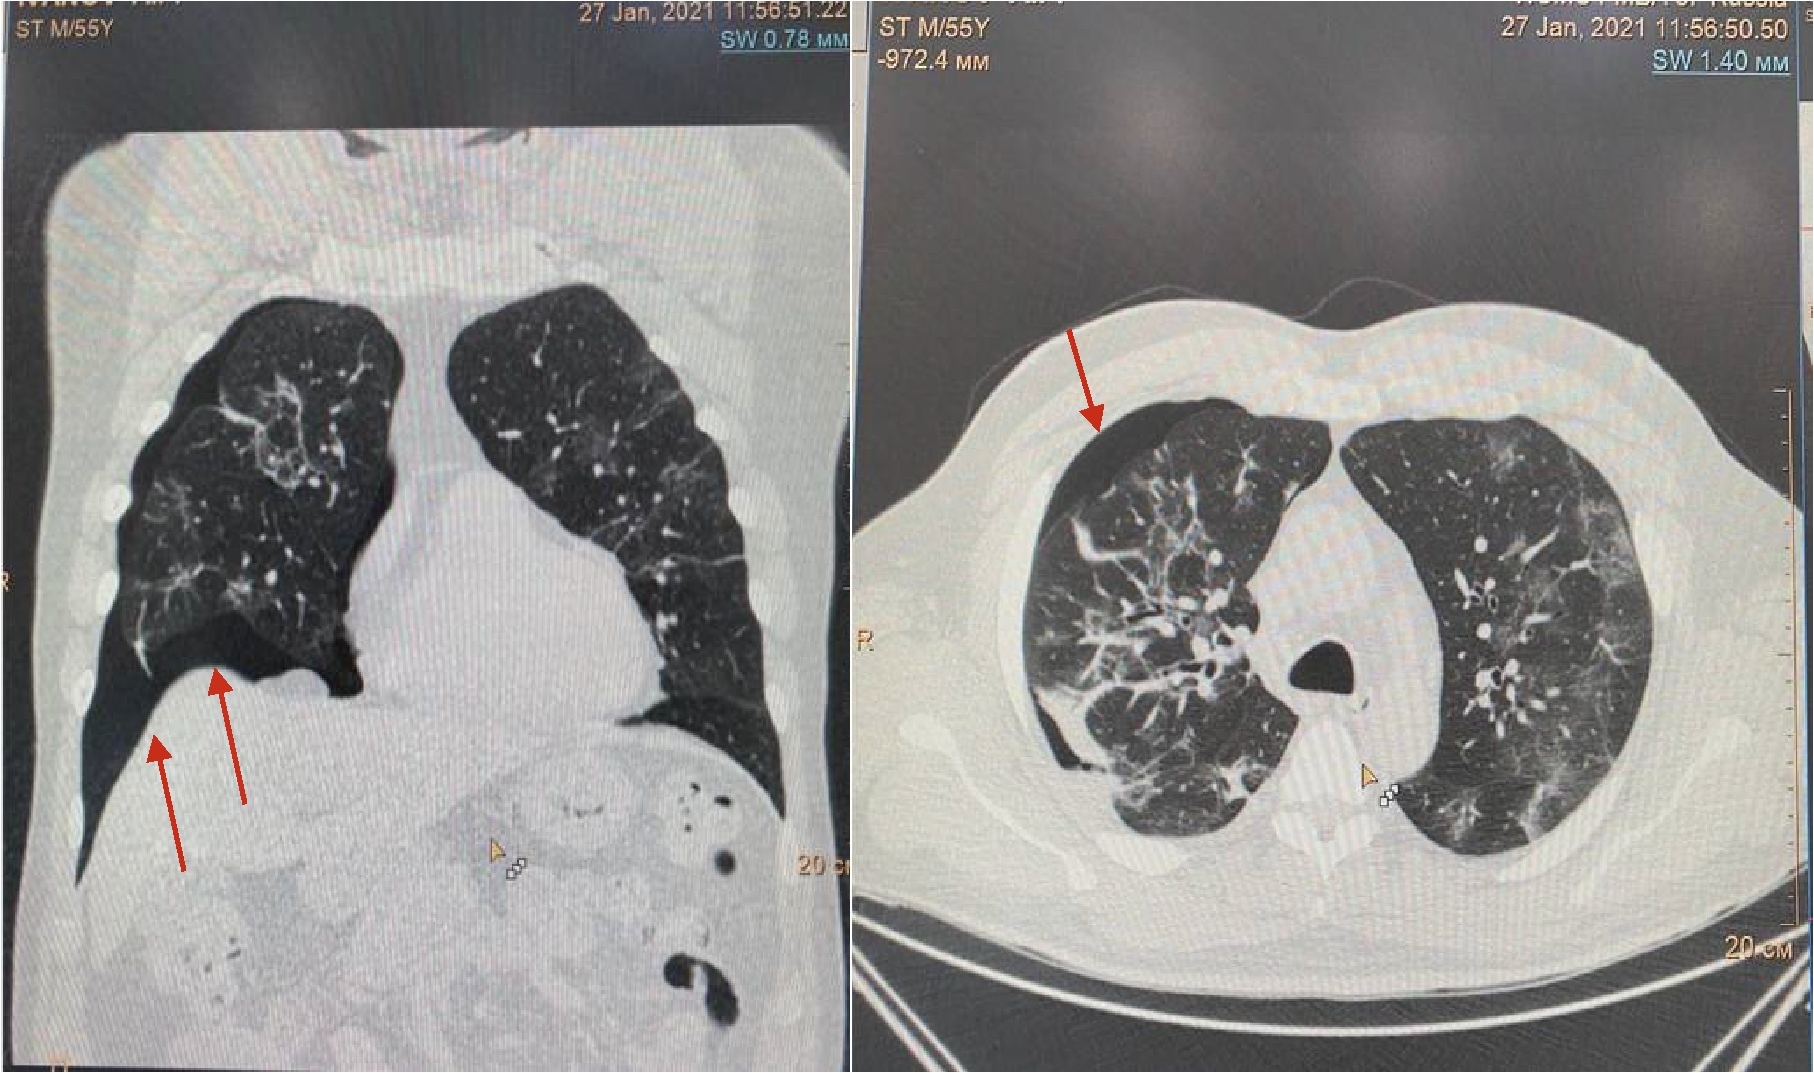

Рисунок 1. МСКТ органов грудной клетки – признаки двусторонней полисегментарной интерстициальной пневмонии (объем поражения 20%, КТ-1).

Пациент (мужчина) 55 лет поступил в стационар с жалобами на сухой кашель, нарушения обоняния и вкуса, одышку при нагрузке, ощущение тяжести в грудной клетке, слабость, боли в мышцах и повышение температуры тела до 380 С. Больной обратился за медицинской помощью на 5 сутки после появления симптомов ОРЗ в связи с неэффективностью самостоятельного лечения и появлением одышки. При поступлении по данным МСКТ легких – признаки двусторонней полисегментарной интерстициальной пневмонии с объемом изменений в пределах 20%, КТ-1 (рис.1). Короновирусная инфекция была подтверждена результатами ПЦР. При поступлении состояние было расценено как средне-тяжелое.